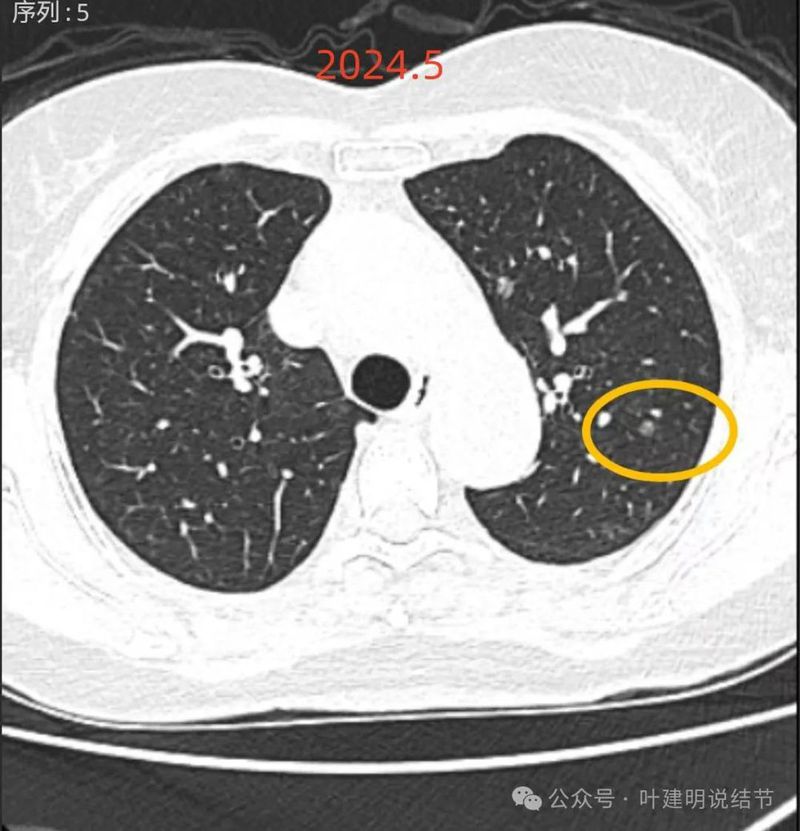

再看2024年5月时的影像:

病灶8:右中叶混合密度结节,较前实性成分增多,边缘毛刺明显起来,考虑浸润性腺癌可能性大;

病灶9:右中叶实性结节,较2021年无明显进展,考虑良性可能性大些;

病灶10:右下叶基底段混合密度结节,有血管穿行,轮廓与边界清,考虑原位癌或微浸润性腺癌可能性大。

两肺多发磨玻璃结节,部分是混合密度。主病灶是红色这处在左上叶的,对比2021年有明显增大进展,考虑是浸润性腺癌可能性大,或者微浸润性腺癌;粉色的考虑原位癌可能性大;橘色的考虑不典型增生可能性大;黄色的考虑肺泡上皮增生可能性大;紫色的考虑微浸润性腺癌可能性大;绿色的考虑良性的可能性大;蓝色的考虑浸润性腺癌或者微浸润性腺癌;黑色的是2021年的时候比较明显的几处病灶。总体对比来看红色的范围增大比较明显,实性成分也有增加;蓝色的密度增加比较明显。首先考虑是多原发早期肺癌。个人觉得继续随访存在一定风险,当然由于病灶太多,也不是说都靠外科手术能够解决问题的,但是主要的有风险的病灶如果能够手术还是需要手术先解决,其他次要的病灶后续再考虑消融或者其他治疗。我的想法是先做右肺下叶背段切除(紫色,考虑微浸润或浸润)加上叶楔形切除(蓝色),下叶粉色的也可楔切或不切;之后看恢复情况过三个月左右再做左肺上叶切除。其余病灶后续如果随访进展考虑消融控制。意见供参考!为何先建议做右侧:先做右侧是因为右侧切得少,到时候再切左侧的时候,单肺通气更能耐受。如果先做左侧,下次做右侧时,左下叶单肺通气不太能耐受些。而且蓝色这处密度增加明显,又贴着胸膜,它的风险相对来说也较高,或许比左上红色的还高点。所以先做右侧。若非转移,靶向药个人不太建议吃,又不是晚期,是多原发早期肺癌可能性大呀。